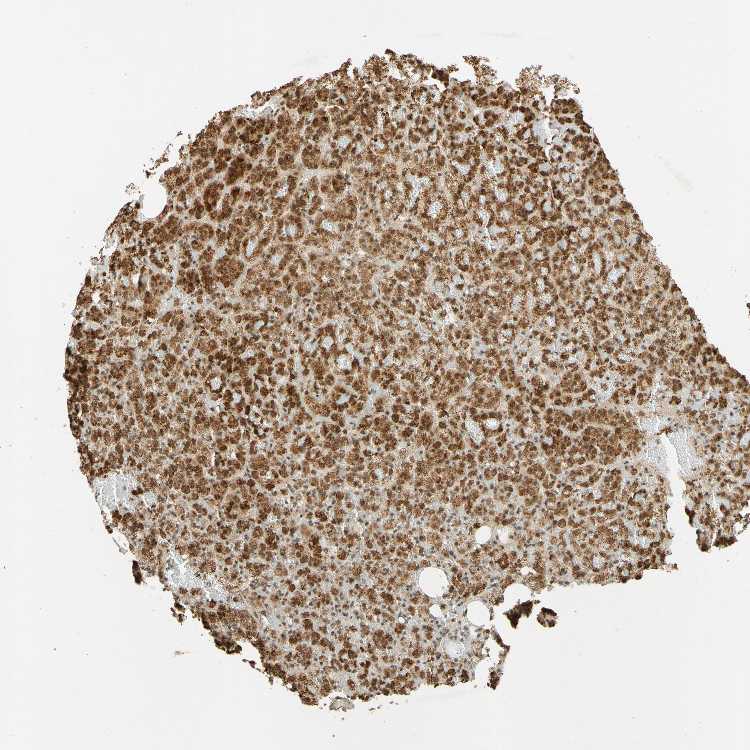

ADRENAL GLAND - Antibody stainingi

Antibody staining in the annotated cell types in the current human tissue is reported as not detected, low, medium, or high, based on conventional immunohistochemistry profiling in selected tissues. This score is based on the combination of the staining intensity and fraction of stained cells.

Each image is clickable and will lead to virtual microscopy that enables deeper exploration of all samples and also displays staining intensity scores, fraction scores and subcellular localization as well as patient and tissue information for each sample.

Antibody HPA018248Antibody HPA019127Antibody CAB009196

Glandular cells HighHighMedium